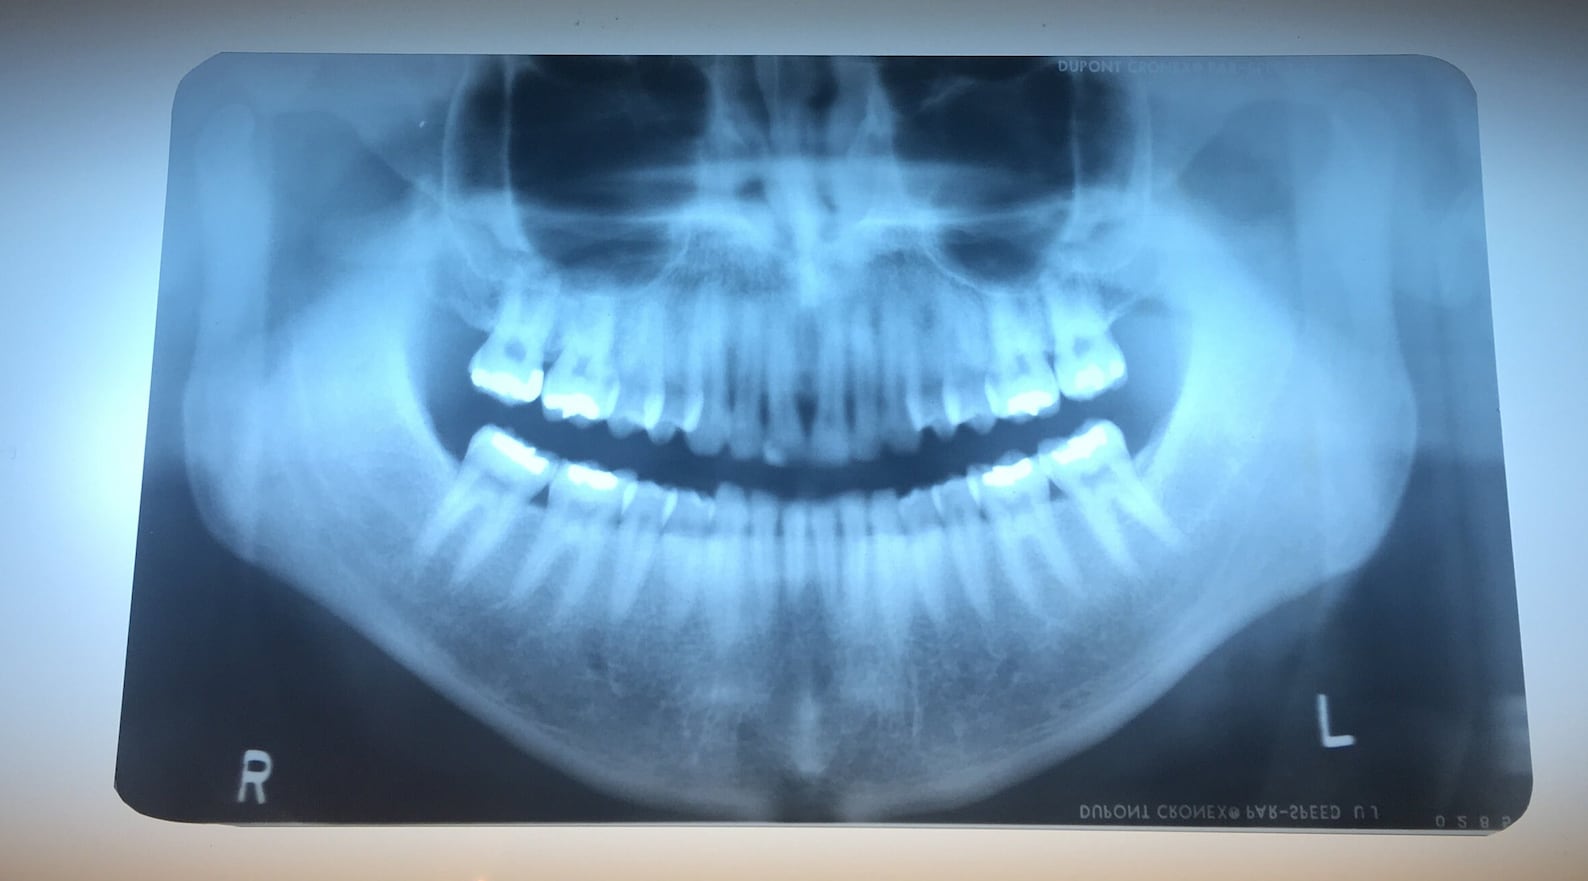

Conventional Dental Films . Types of digital imaging systems. it addresses topics such as patient selection criteria, film selection for conventional radiographs, collimation, beam filtration, patient protective equipment, film holders, operator protection, film exposure and processing, infection control, quality assurance, image viewing, direct digital radiography and continuing education of dental health. For digital systems, dd imaging was superior. technological advancement of conventional dental film is aimed at producing faster films without sacrificing the image quality of. the aims of the present study were (1) to evaluate the diagnostic accuracy of enamel caries lesion detection using. next, to estimate the length of the canal for each tooth, three radiography methods. therefore, the purpose of this study is to compare periapical radiographs.

From www.etsy.com

Vintage Dental Xray Films Panoramic Etsy Conventional Dental Films technological advancement of conventional dental film is aimed at producing faster films without sacrificing the image quality of. next, to estimate the length of the canal for each tooth, three radiography methods. it addresses topics such as patient selection criteria, film selection for conventional radiographs, collimation, beam filtration, patient protective equipment, film holders, operator protection, film exposure. Conventional Dental Films.